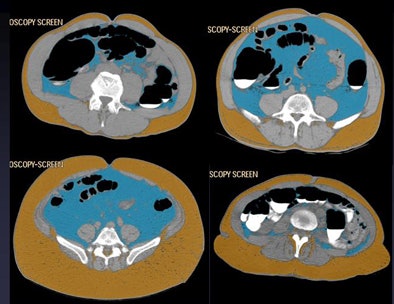

![]() |

| Four patients show different abdominal fat distribution patterns. |